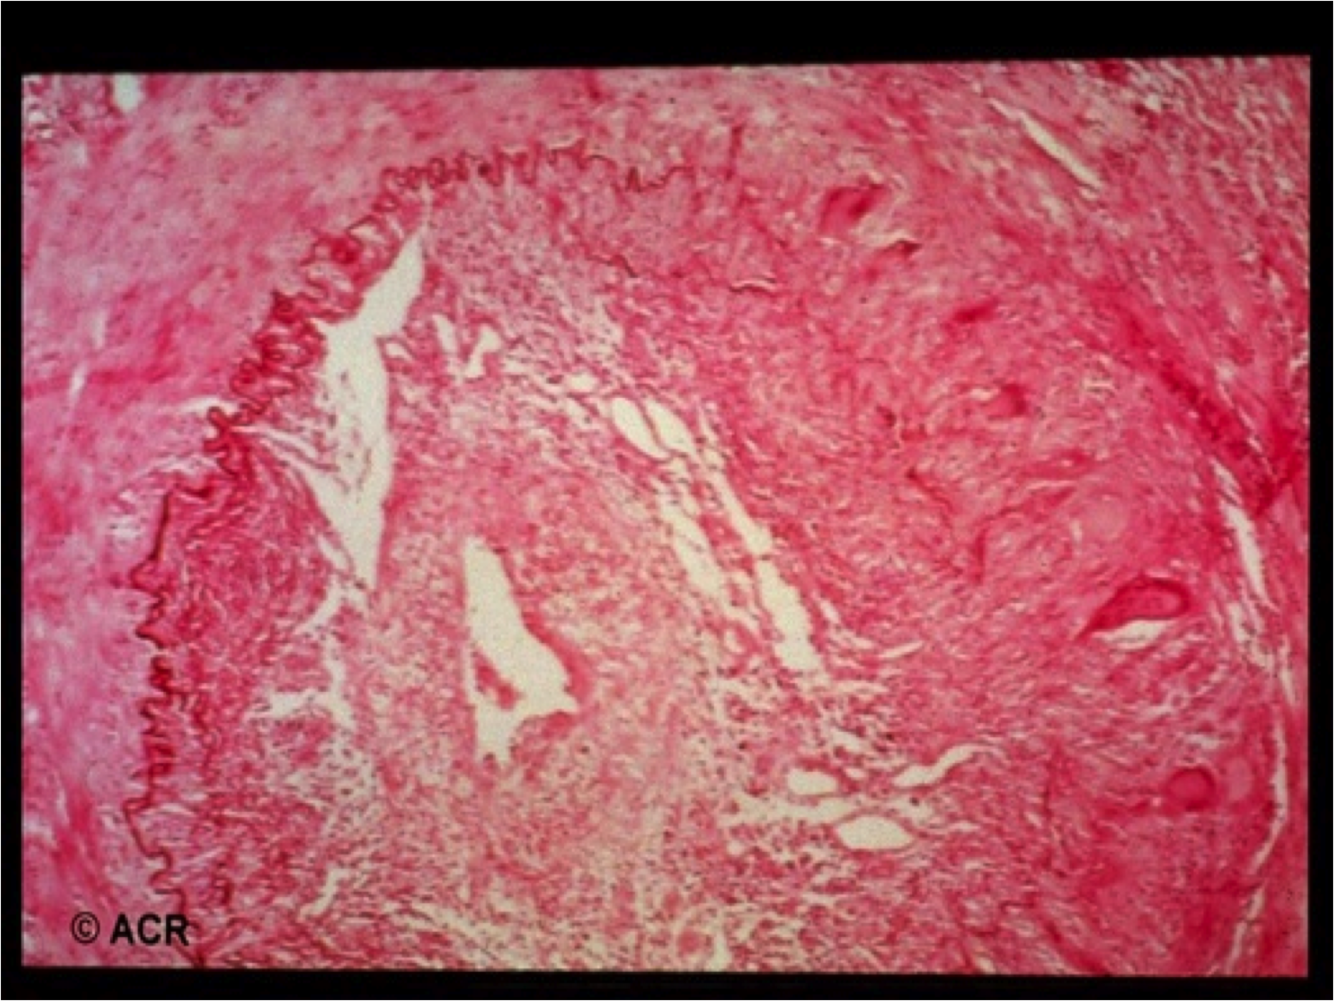

A 70 yo man is seen because of new headaches located where his hat rubs on his temples. He finds his scalp painful when he combs his hair, his vision has momentarily gone black and his jaws hurt to chew steak. He has lost 10 pounds and he has a low grade fever of 100 on a daily basis.

LARGE VESSEL VASCULITIS

Very similar pathology at GCA